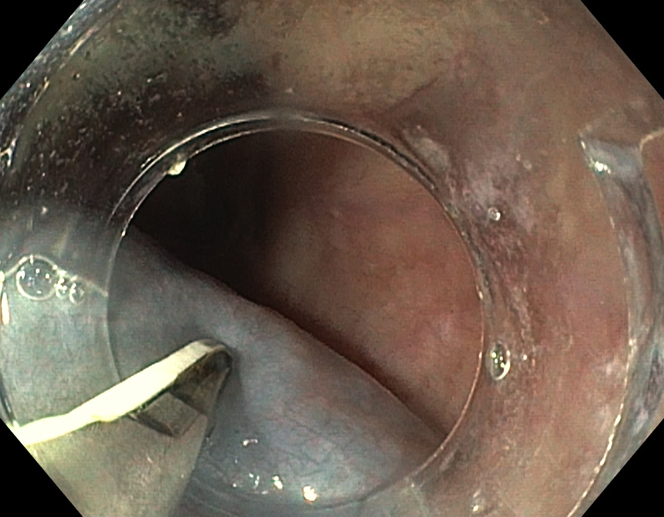

Figure 1.

Submucosal injection by use of a novel device with integrated needle system.